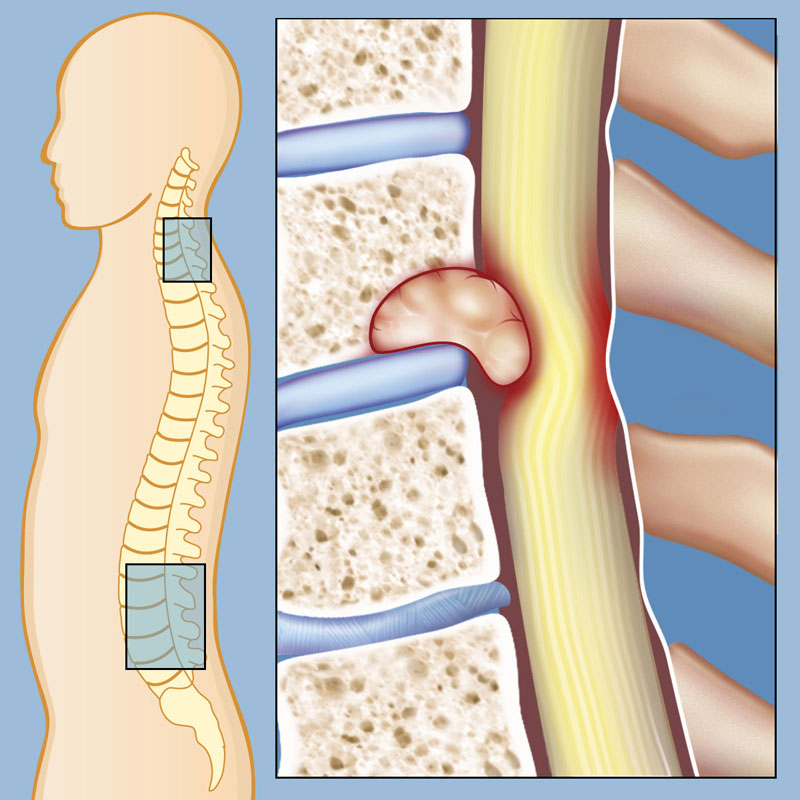

طناب نخاعی یکی از حیاتیترین بخشهای سیستم عصبی بدن است که از پایه مغز به سمت پایین امتداد یافته و پیامهای عصبی را بین مغز و سایر اندامها جابهجا میکند. این ساختار حساس توسط استخوانهای ستون فقرات محافظت میشود. گاهی اوقات، رشد غیرطبیعی سلولها در این ناحیه منجر به ایجاد تودهای به نام تومور نخاعی میشود.

تومورهای نخاعی حدود ۱۵ درصد از کل تومورهای سیستم عصبی مرکزی را تشکیل میدهند. اگرچه بسیاری از این تومورها غیرسرطانی (خوشخیم) هستند، اما به دلیل فضای محدود داخل ستون فقرات، بزرگ شدن آنها میتواند به اعصاب و بافت نخاع فشار وارد کرده و عوارض جبرانناپذیری ایجاد کند. در این مقاله به بررسی کامل انواع، علائم، علل و روشهای درمان این بیماری میپردازیم.

تومورهای نخاعی بر اساس محل قرارگیری آنها نسبت به پرده محافظ نخاع (دورا یا سختشامه) و خود بافت نخاع، به سه دسته اصلی تقسیم میشوند:

۱. تومورهای اکسترادورال (خارج سختشامه)

این تومورها شایعترین نوع هستند و در استخوانهای مهره یا بافتهای خارج از پرده محافظ نخاع رشد میکنند. بیشتر این تومورها ناشی از متاستاز (گسترش سرطان از سایر نقاط بدن مانند سینه یا ریه به ستون فقرات) هستند.

۲. تومورهای اینترادورال-اکسترامدولاری (داخل سختشامه، خارج از بافت نخاع)

این تومورها درون پرده محافظ نخاع قرار دارند اما مستقیماً بافت خود طناب نخاعی را درگیر نمیکنند و معمولاً از ریشههای عصبی یا غشای پوشاننده نخاع منشأ میگیرند. مننژیومها، شوانوماها و نوروفیبروماها از شایعترین نمونههای این دسته هستند.

۳. تومورهای اینترامدولاری (داخل بافت نخاع)

این تومورها که نادرترین نوع (تنها ۲ تا ۵ درصد از کل تومورهای نخاعی) هستند، مستقیماً از سلولهای درون طناب نخاعی (پارانشیم) نشات میگیرند و باعث تخریب بافت خاکستری و سفید نخاع میشوند. شایعترین انواع آنها عبارتند از: